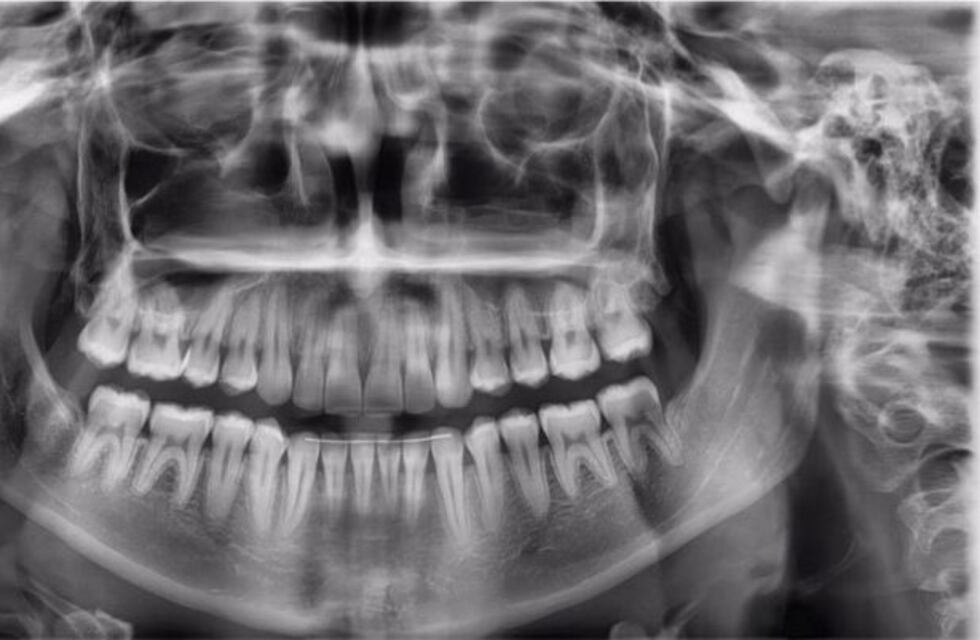

En la localidad de Río Ceballos, el Centro Odontológico "Arquitectura Bucal" ofrece el servicio de radiografiás e imágenes en HD denominado Pano.

El mismo permite realizar capturas panorámicas de radiografías bucales y teleradiografía de frente y perfil.